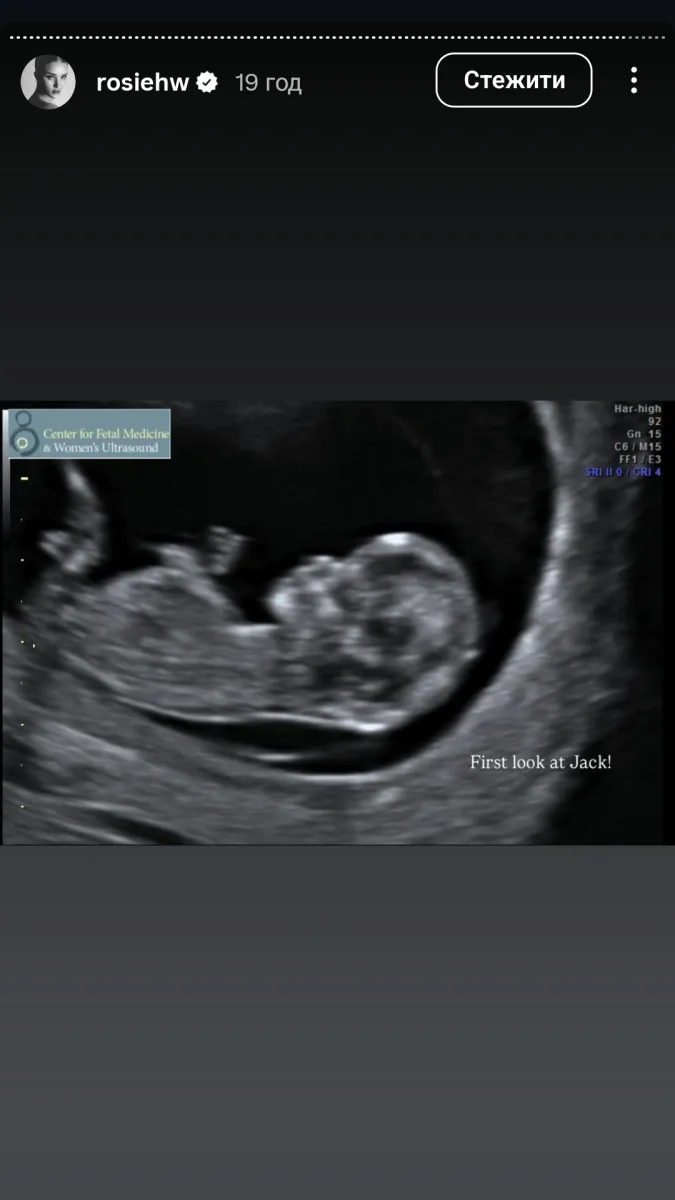

УЗД. Фото: Іnstagram

Модель навіть показала перше УЗД, а також своє фото з невеличким животом.